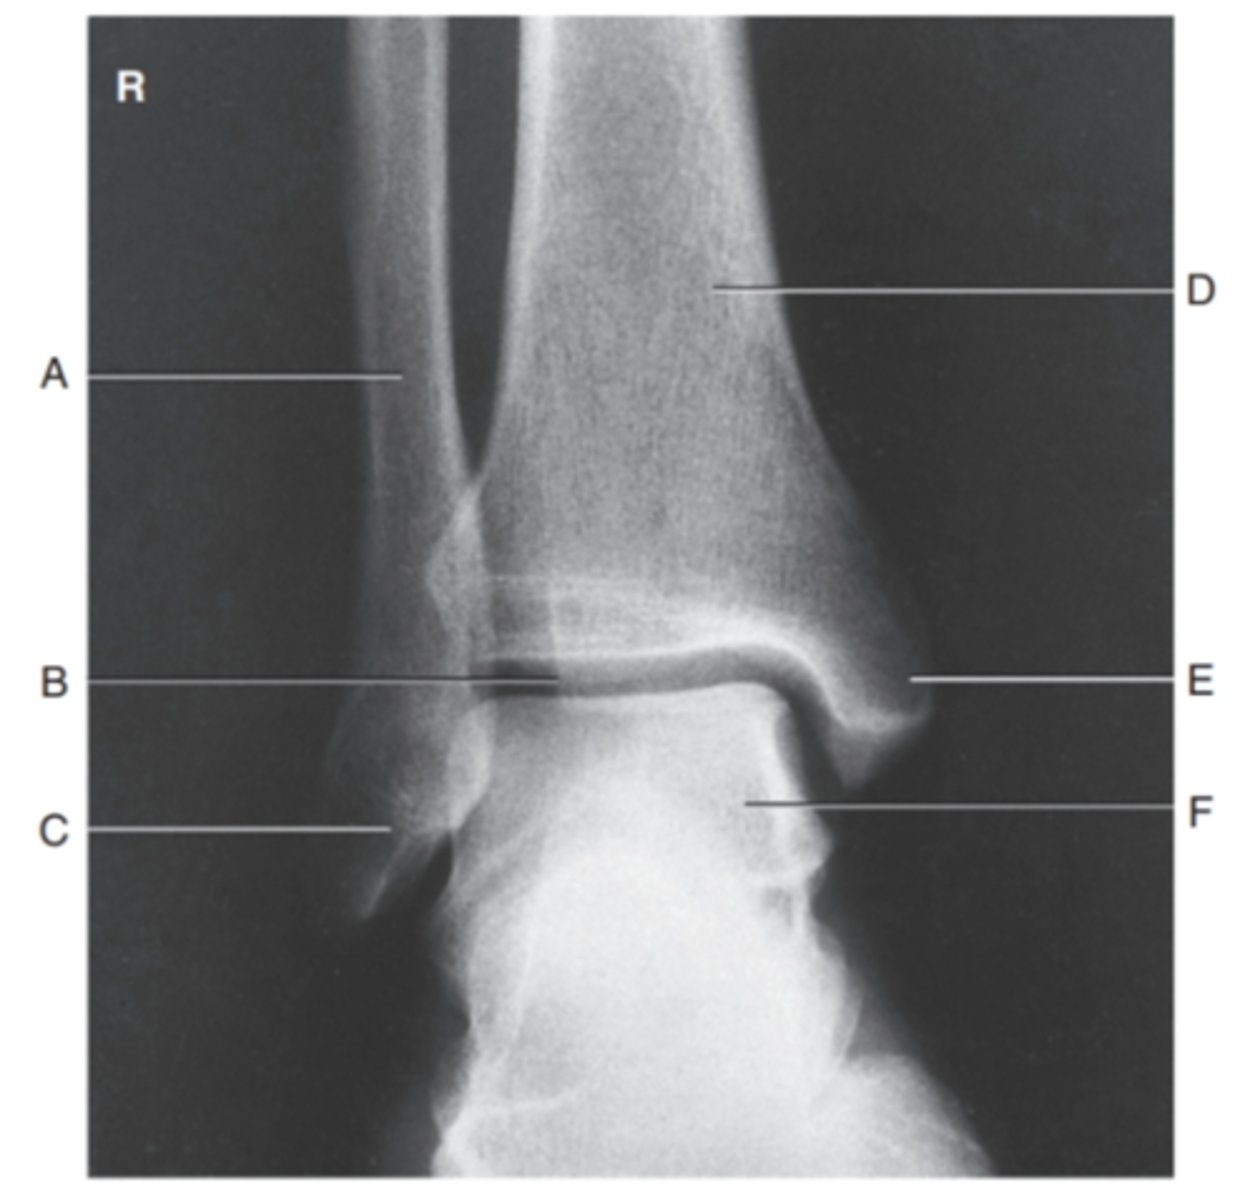

(MORTIS AP ANKLE) what is A?

fibula

what is B?

lateral malloelus

what is C?

tibia

what is D?

medial malleolus

what is E?

motrise joint

what is F?

talus